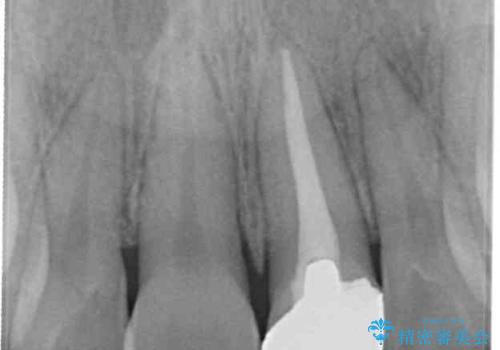

- 前歯の歯並びと不自然な色をした前歯のクラウンを気にして来院された患者様です。

上下前歯の歯列不正はインビザラインにより歯列を整え、その後に、前歯をオーダーメイドタイプのオールセラミッククラウンにて補綴治療することとしました。

初診時には、歯並びを整えることのみを検討されていましたが、歯列が整うにつれて不自然な色合いが気になるようになり、矯正治療を行ってから補綴治療をする計画を受け入れてくださいました。